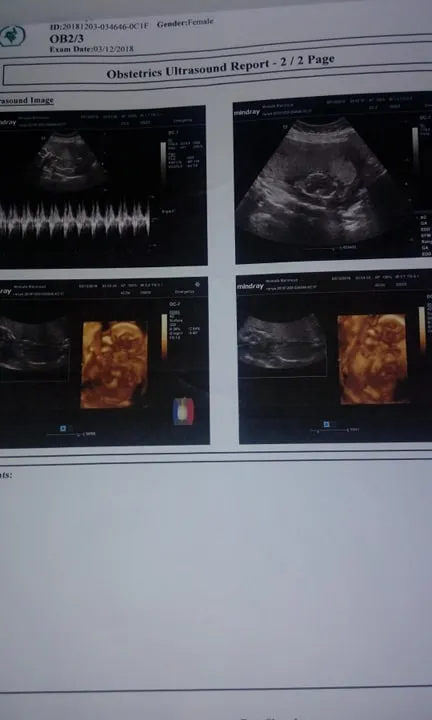

بدأت "ر. ج" حديثها، قائلة إنها حملت بتوأم، فكانت نهايتها المأسوية على يد طبيب النساء والتوليد، فلم يشأ القدر أن تنجب توأمها لأن التشخيص الطبي أكد نقص الماء حول الجنين في الشهر السادس من الحمل، فذهبت إلى طبيب نساء وتوليد لإجراء عملية إجهاض، فكانت النتيجة مأسوية وتحولت لكابوس يهدد حياتها.

الضحية روت مأساتها لـ" محرري الفجر"، قائلة "يوم 13/12/2018 ذهبت لطيب نساء وتوليد يدعى (محمد.أ) لإجراء عملية إجهاض للجنين بعد تأكييد التشخيص الطبي أثناء الحمل فى الشهر السادس جفاف الماء المحيط بالجنين ووجود عيب خلقى، وأن العلاج الوحيد عملية إجهاض".

وتضيف السيدة لـ"الفجر"، عندما ذهب فى اليوم الثاني تفاجأت أنه طالب الممرضين بتحضير غرفة العمليات دون استكمال التحاليل، وعندما سألته عن سبب عدم استكمال التحاليل، رد عليا (لا ده مش شغلك)، وبالفعل خضعت لإجراء العملية مع العلم أني لا أعلم وجود توأم فى بطني والطيب تعامل مع حالتي على أنه طفل واحد فقط".

"منظار" الذي أوضح أنه فيه بواقي عظم"، أكملت "ر.ج"، حديثها بالقول إن بقايا عظم الجنين مازال داخل أحشائها، وأن المنظار الذي أوضح وجود البقايا، والسونار لم يوضحها.